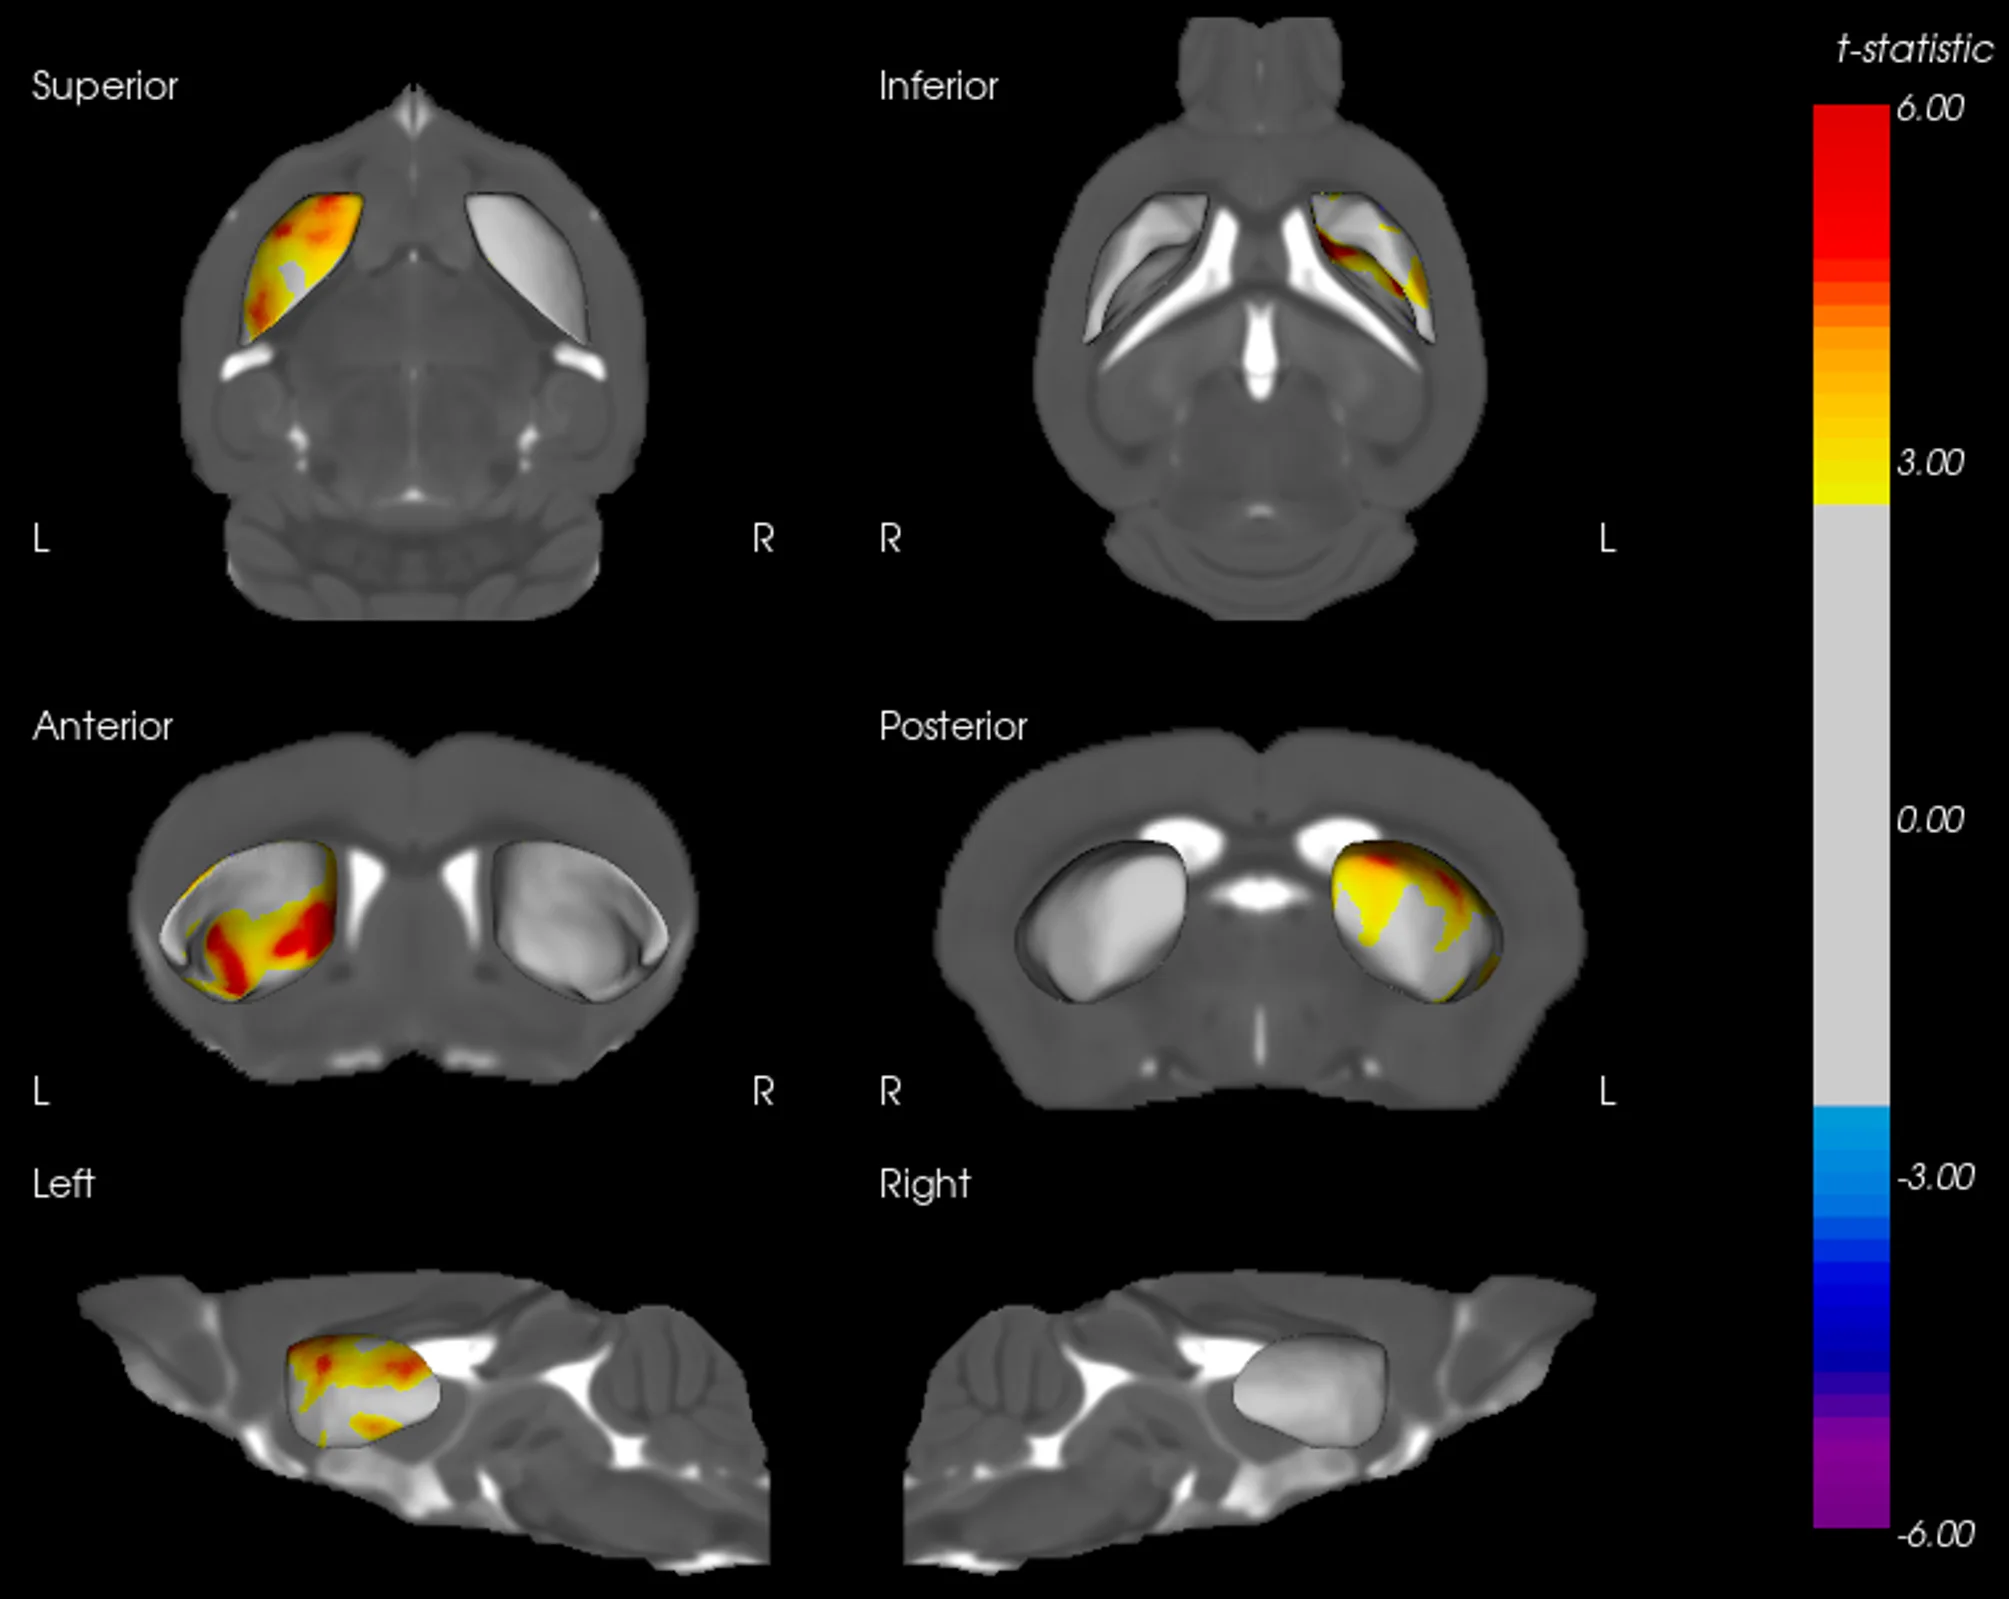

AAV-Tau 小鼠纹状体表面变形

纹状体的三维表面渲染图,显示 AAV-Tau 注射小鼠左半球向内变形的局部区域。冷色表示与向内位移相对应的具有统计学意义的负t统计量。变形仅限于同侧,与 tau 诱导的萎缩一致。

纹状体变形与 TH 密度之间的相关性

纹状体表面变形图与相应的 TH 密度相关性的叠加。暖色区域代表具有显著正 t 统计量的区域,表明局部表面变形与 TH 标记密度之间存在密切关系。这些区域突显了 AAV-Tau 小鼠的多巴胺能神经支配区。